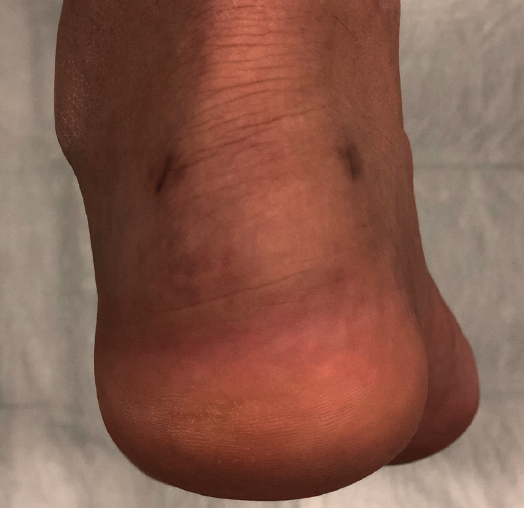

Magnetic resonance imaging (MRI) allows us to evaluate the presence of intratendinous injuries, fluid collections, the appearance of the bursae, bone edemas in the posterior tuberosity, and to establish the differential diagnosis with other disease conditions(22)(Figure 5). If the plain radiographs and ultrasound findings are conclusive, MRI is not essential. In the absence of an experienced ultrasound operator, or if there are doubts after ultrasound regarding the presence of disease in the tendon and bursa, MRI is very useful.

Figure 5. Magnetic resonance imaging. Retrocalcaneal bursitis. Fluid in the retrocalcaneal recess without signs of degenerative tendinopathy.